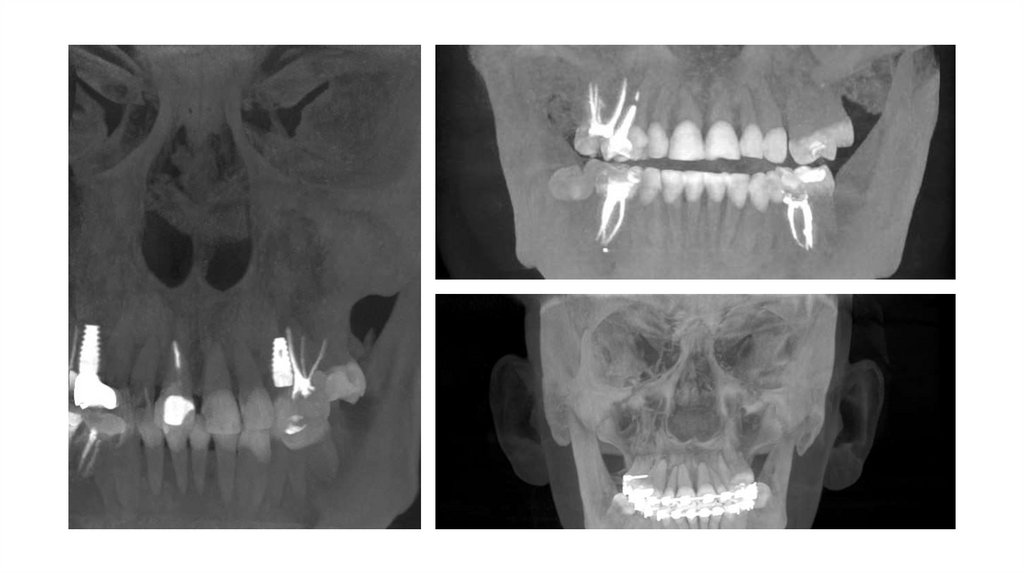

3. Обзор методологии Как модель рассматривает результаты сканирования?

4.

Stage 1: First Detection

Stage 2: Making the U-cut

5.

Stage 3: Teeth incentive

selection

Stage 4: Final Selection